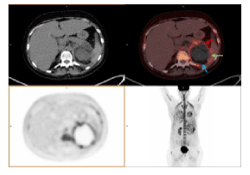

A month later, due to the progression of symptoms and an inconclusive lung function result, a new 18F-FDG PET-CT was performed and showed the above-described ametabolic kidney lesion increased in size, which now involved the whole left kidney (Figures 2A and 2B), as well as the pancreatic toe and spleen (Figure 3). A biopsy of perirenal hypermetabolic tissue, guided by PET/CT findings, was performed and histopathology showed abundant elongated structures in the form of thick, non-septate hyphae, with branches at right and obtuse angles, which with Grocott's silver stain showed thick contours (Figure 4). These findings lead to the final diagnosis of mucormycosis caused by Rhizopus oryzae. Due to involvement of such organs and the difficulty of its surgical debridement, the patient received medical treatment based on amphotericin B and Isavuconazole.

Figure 2. Second 18F-FDG PET-CT after SCT. The lesion previously informed as a probable renal infarction has increased and now affects the whole kidney, as seen in CT and PET/CT fusion images

Figure 3. Second 18F-FDG PET-CT after SCT. An ametabolic lesion, with periferal uptake of 18F-FDG involves left kidney (blue arrow), spleen (Green arrow) and pancreatic toe (red arrow). These findings guided biopsy study, which lead to the final diagnosis of mucormycosis